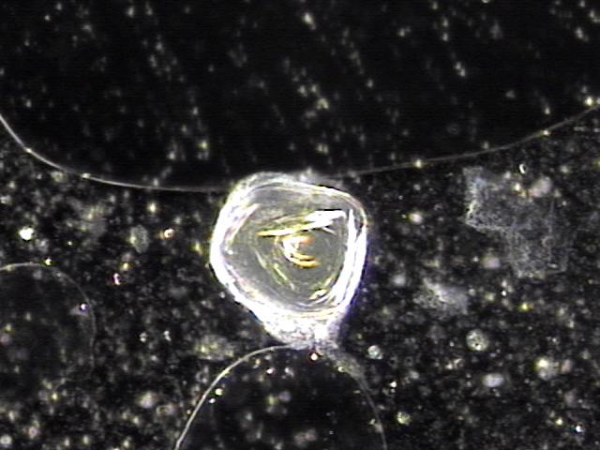

주2회 전립선의 표적 치료후 치료된 상피 세포 덩어리의 현미경학적 자료입니다.

"This is the microscopic data of the epithelial cell clusters treated after targeted prostate therapy twice a week."